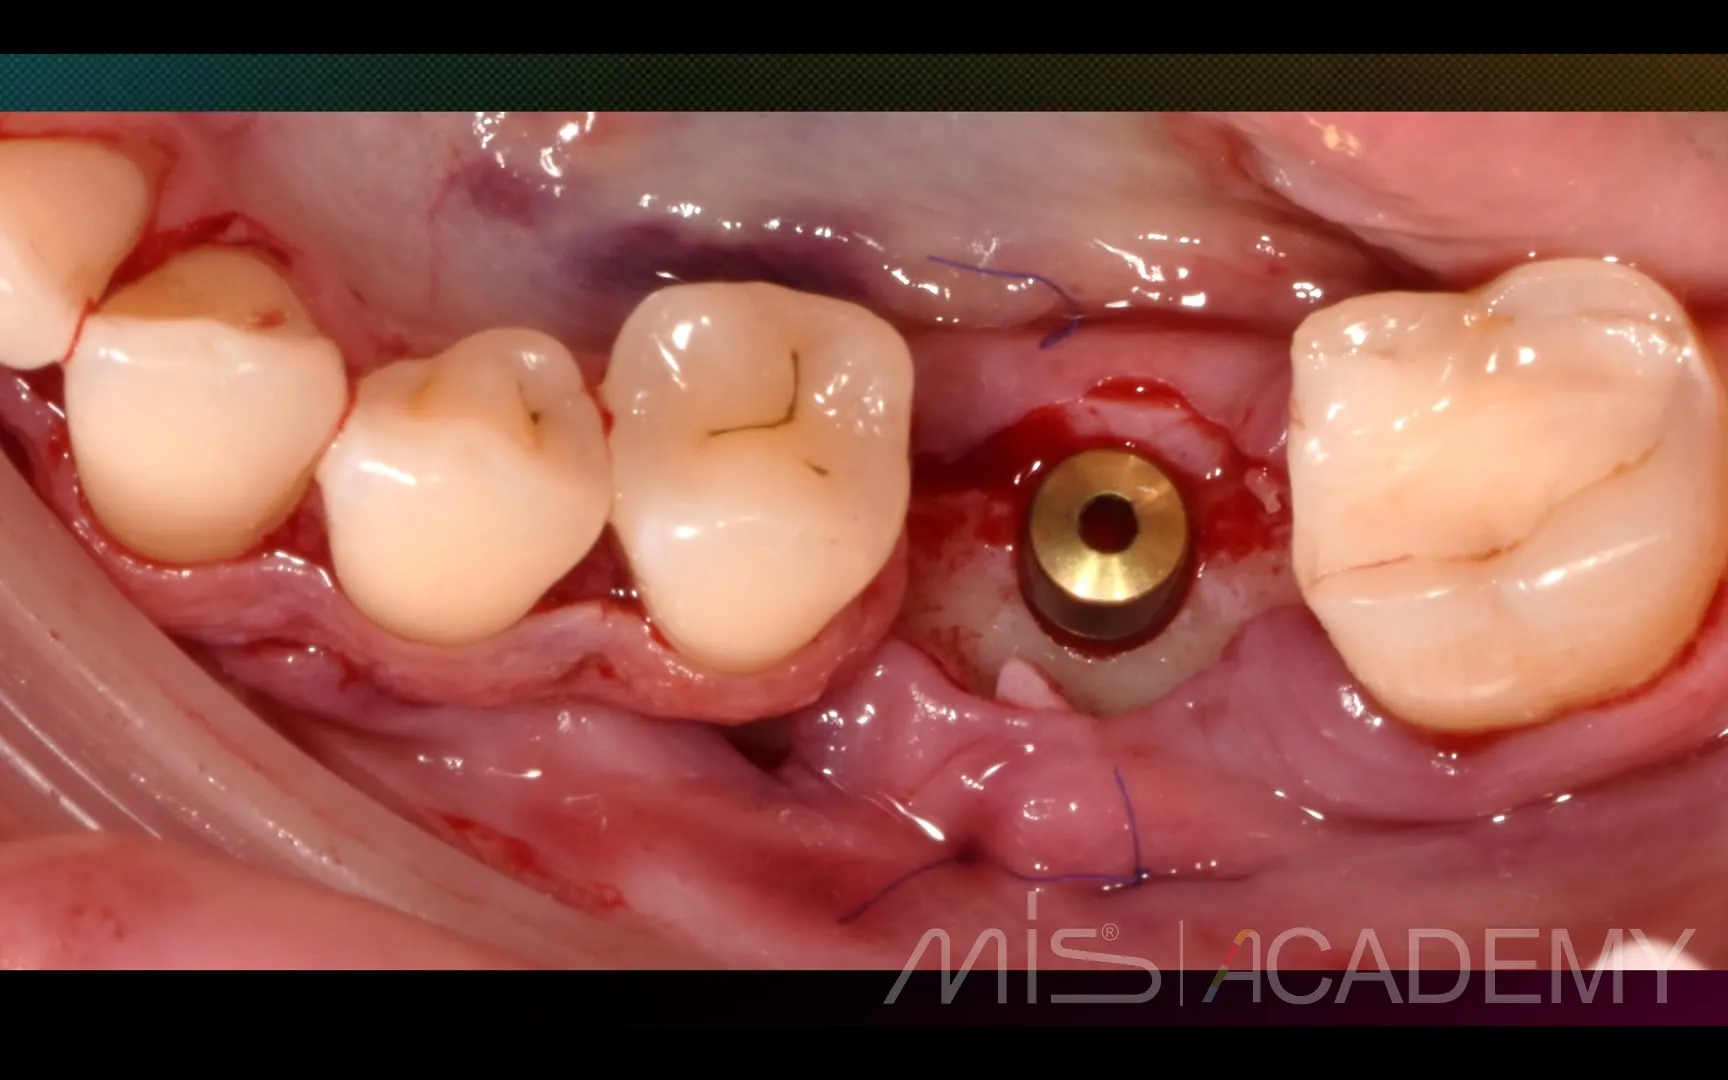

Промежуточный результат клинического кейса одномоментного закрытия рецессий и установки имплантата MIS C1 с CONNECT абатментом.